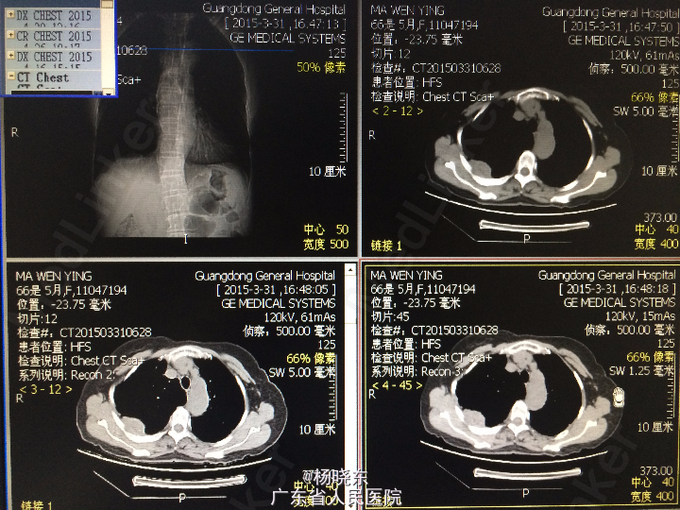

主诉:反复胸背痛1年,加重1月。 病史:患者1年前无明显诱因出现右侧胸背痛,性质为隐痛,无向周围放射。遂至当地医院门诊就诊,查胸部CT,考虑“胸膜肿瘤”,建议手术处理,但患者拒绝未予治疗,症状持续数天后自行消失。后间断出现类似症状,但均可忍耐。1月前患者自觉右上肢上抬及抬举重物时右侧胸背痛明显,不伴有其余部位牵涉痛,未予重视。近1周来,患者自觉症状加重,疼痛致右上肢不可上抬,弯腰时加重,平卧时可缓解。现为进一步手术治疗入院,无发热,无头晕、头痛,无咳嗽、咳痰,无气促、心悸,无恶心、呕吐,无腹痛、腹泻,无皮疹、无双下肢浮肿。自起病以来,精神、睡眠可,食欲可,二便正常,体重近1月下降2kg。

查体:右侧胸肋部及肩胛区压痛明显。 辅查:胸片,CT。

诊断:胸膜间皮瘤 处理:右侧胸膜肿瘤切除术

术中病理显示为结核脓肿,改行右侧胸膜结核性脓肿扩大清除术+右肺楔形切除术。 术后予加用异烟肼+利福平+乙胺丁醇联合抗结核治疗。